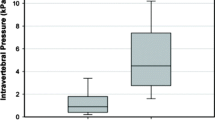

Intradiscal pressure

After vertebral fracture IDP in the neutral position was reduced to 56 % (P < 0.001) of the pre-fracture level, to 58 % in flexion (P < 0.001) and to 48 % in extension (P < 0.001). IDP increased after the first injection in the neutral position to 64 % (P < 0.05), remained the same after the second injection and again increased to 71 % (P < 0.001) after the third. After the fourth injection there was no statistically significant increase of IDP. The results were similar in the flexion position: after the first injection IDP increased to 65 % (P < 0.05), remained the same after the second injection and increased to 69 % (P < 0.001) after the third. After the fourth injection IDP increased to 71 %; this increase was not statistically significant. In extension, there was significant increase in IDP only after the forth injection of cement, with IDP reaching 58 % of the pre-fracture level (P < 0.05) (Table 2, Fig. 3).

According to our study model, vertebroplasty with PMMA cement fill cannot restore IDP and compressive stiffness of an FSU to pre-fracture level with cement fills up to 20 % of the vertebral body volume. Fifteen per cent of cement fill was the limit beyond which no substantial increase in compressive stiffness and IDP was detected. We recommend that cement fill for vertebroplasty should be 15 % of fractured vertebral body volume which in concordance with average thoracolumbar vertebral body volumes for men and women [30] corresponds to 4–6 ml of cement fill depending on the vertebral level. In spite of the fact that our study was purely in vitro, we suggest that this rule can be applied clinically.